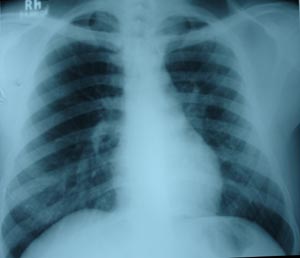

Left mid zone Koch’s infection 7

Right mid zone shows very few fibronodular opacity, suggestive old koch’s infiltration. AKT stopped after stipulated time.